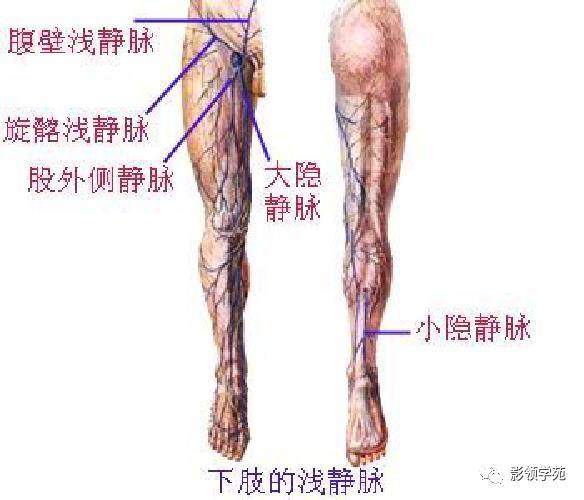

心血管系统

腹部动静脉

心血管系统

腹部动静脉